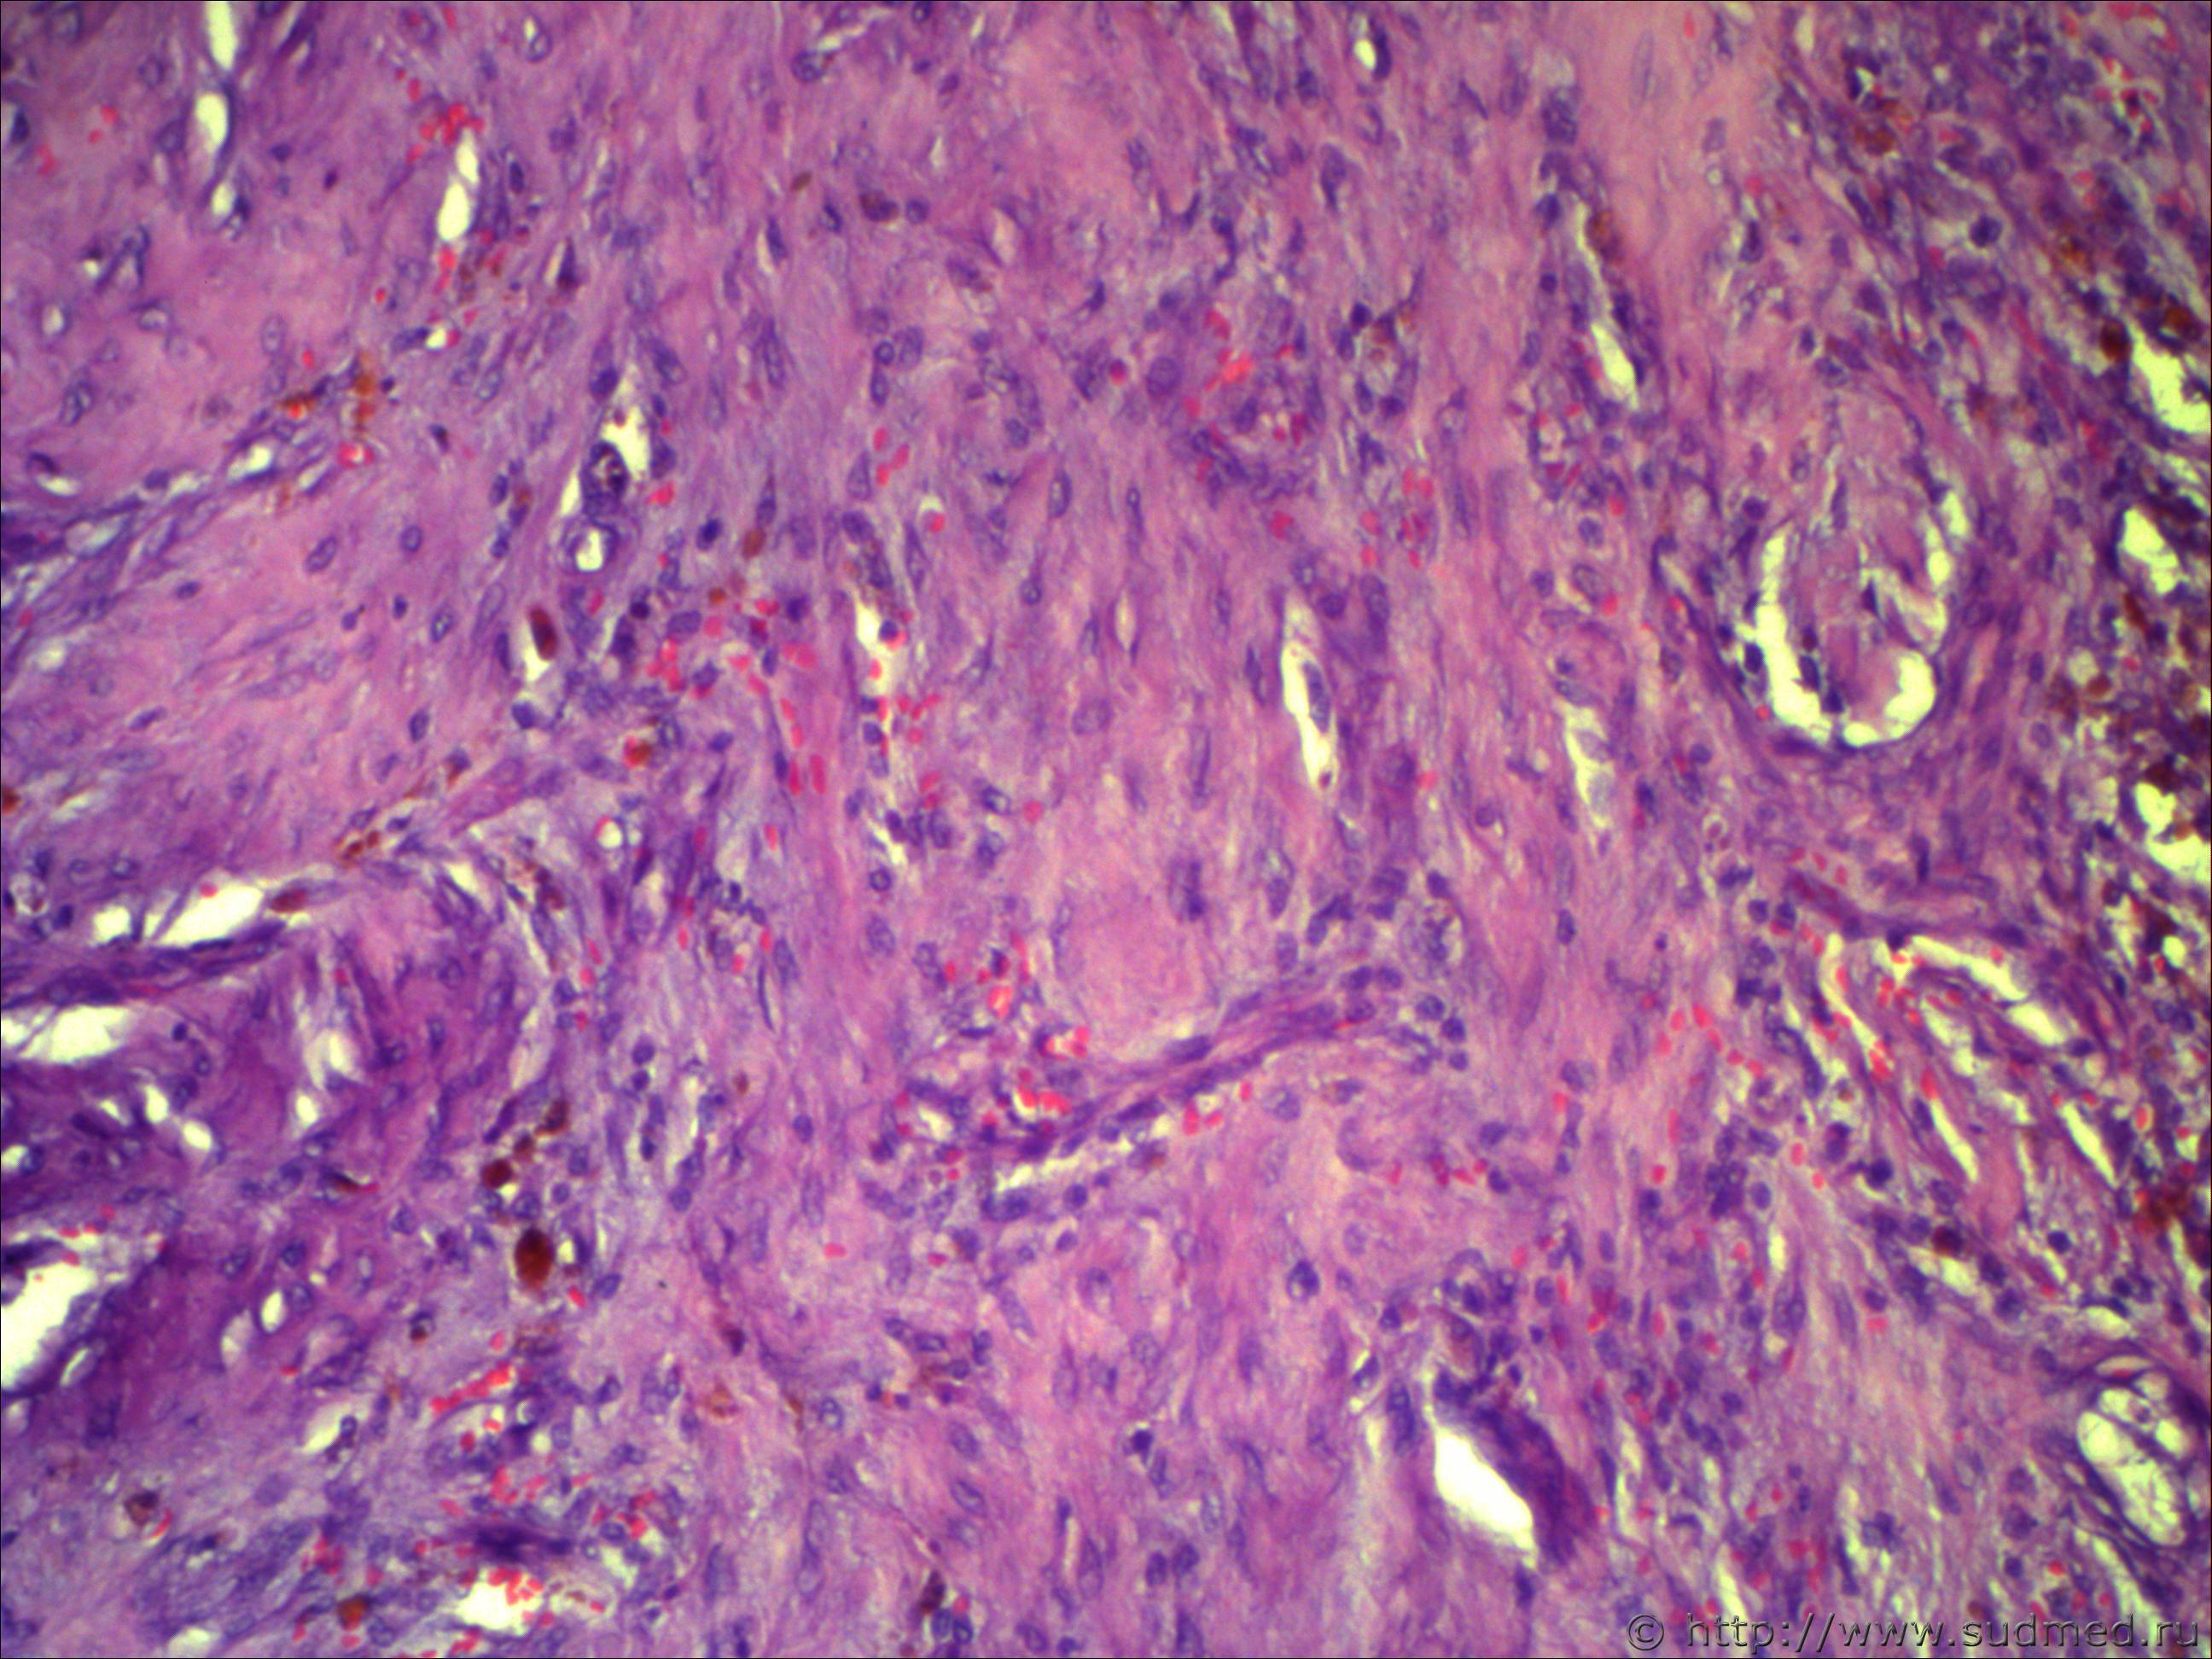

Н/О округлой формы четких границ, на теле фибринозно-кистозной структуру 5*7см!

Похоже на ангиофиброму.

Не фибринозно, а фиброзно-кистозная структура. Пока об ангиофиброматозе нужно думать, требует дальнейшей дифференциации.Срезы толстые. Наблюдается эндотелиальная пролиферация...

Ничего такого не понял, вижу:

- новообразование сосудов. полнокровие очаговое

- очаговый гиалиноз

- смешанную фиброму (типическую)... да их столько с примесью кистозного элемента

- митозов не вижу